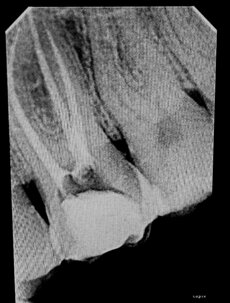

Benvenuti nella nostra sezione dedicata all'endodonzia, un ramo specialistico che si occupa della cura del tessuto molle interno del dente, noto come polpa. L'endodonzia è cruciale quando la polpa diventa infiammata o infetta, e il trattamento tempestivo può preservare il dente, evitando ulteriori complicazioni.

L'infiammazione della polpa può portare alla formazione di un ascesso dentale, una tasca di pus che può causare gonfiore, dolore e, se trascurato, può diffondersi ai tessuti circostanti. L'endodonzia mira a trattare l'infezione alla radice, eliminando il rischio di ascesso.

Se non trattata, l'infiammazione della polpa può portare alla perdita del dente. La devitalizzazione è spesso l'ultima risorsa per preservare il dente, eliminando la fonte di infezione e ripristinando la sua funzionalità.